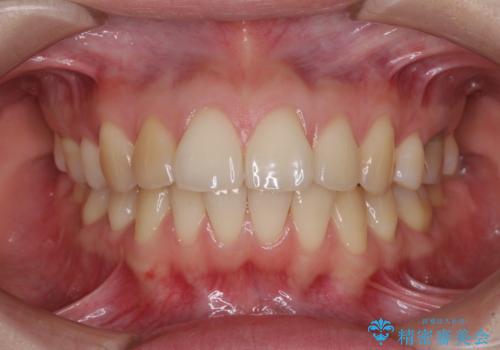

![[インビザラインモデレート] 抜歯矯正後の後戻り 出っ歯を治したいの症例 治療前](https://seimitsushinbi.jp/wp/wp-content/uploads/2025/05/IMG_4903-500x350.jpg?v=1746627186)

インビザライン・モデレートを用いて気になる後戻りを矯正治療

前歯のガタつきを改善 抜歯矯正後の後戻り